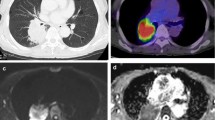

A total of 116 patients with lung cancer were enrolled (26 females, 90 males; mean age 61.00 ± 8.30 years, range 39–77 years). Among them were 81 cases with NSCLC (47 patients with Adeno-Ca and 34 patients with SCC; 39 patients without LNM and 42 patients with LNM) and 35 cases with SCLC. The determination of pathological subtypes and LNM status relies on pathological examination. The patients were categorized into the Adeno-Ca, SCC, and SCLC groups. Patients with NSCLC were further subdivided into the LNM (+) and LNM (−) groups based on their lymph node status. Table 2 summarizes the clinicopathologic characteristics of the patients. Representative cases are shown in Fig. 2.

A 58-year-old male patient with SCC. a Axial image of T2-BLADE; b–e IVIM parameters ADC, D, D*, and f maps; f native T1 pseudo-color map; g postcontrast T1 pseudo-color map; and (h) pathologic picture (HE × 10). ADC, apparent diffusion coefficient; D, true diffusion; D*, pseudo-diffusion; f, perfusion fraction; HE, hematoxylin and eosin; IVIM, intravoxel incoherent motion